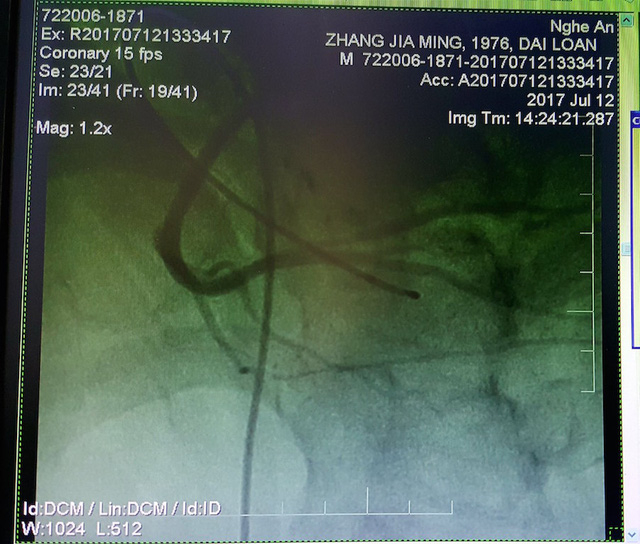

Hình ảnh chụp mạch cho thấy, động mạch vành phải của bệnh nhân hẹp tắc hoàn toàn từ RCA-II. Ngay lập tức, bác sỹ Tim mạch tiến hành hút huyết khối và can thiệp đặt stent vào động mạch vành, kịp thời cứu bệnh nhân qua cửa tử.